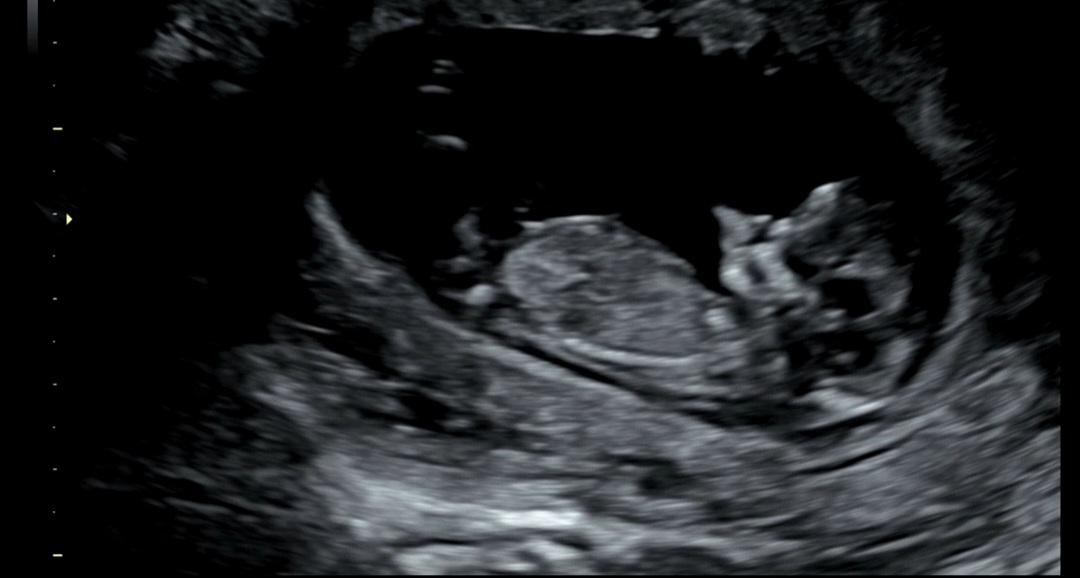

12주1일 각도법

재미로 각도법 한번만 봐쥬 >_<